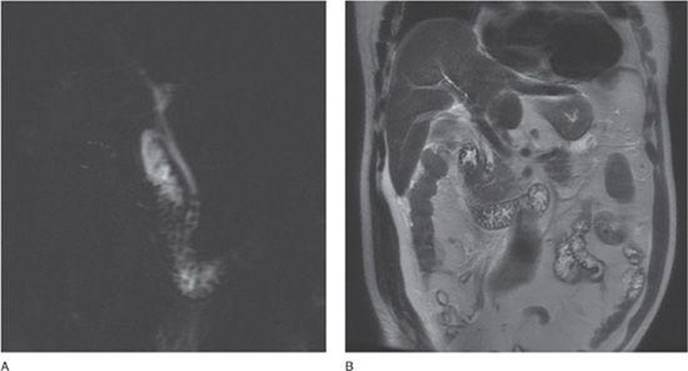

Which imaging study demonstrated in Figure 39-4 is comparable to ERCP for detecting choledocholithiasis?

Figure 39-4

Endoscopic ultrasound (EUS) has a positive predictive value of 99%, a negative predictive value of 98%, and accuracy rate of 97% for detecting choledocholithiasis compared to ERC. Magnetic resonance cholangiopancreatography (MRCP) shown in the Figures 39-5A and B is the next best test with sensitivity and specificity of 93% and 94%, respectively.

Figure 39-5A, B